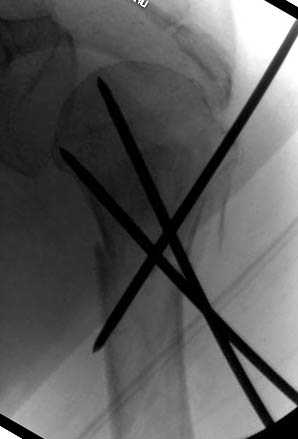

Наш недавний случай перкутанной фиксации "методом

Сиэтла" спицами 2.8 мм с резьбой на конце.

Наличие рентген контроля (ЭОП) помогает во время

репозиции и фиксации, но многие коллеги умудряются без рентгена

фиксировать несколькими спицами перкутанно.